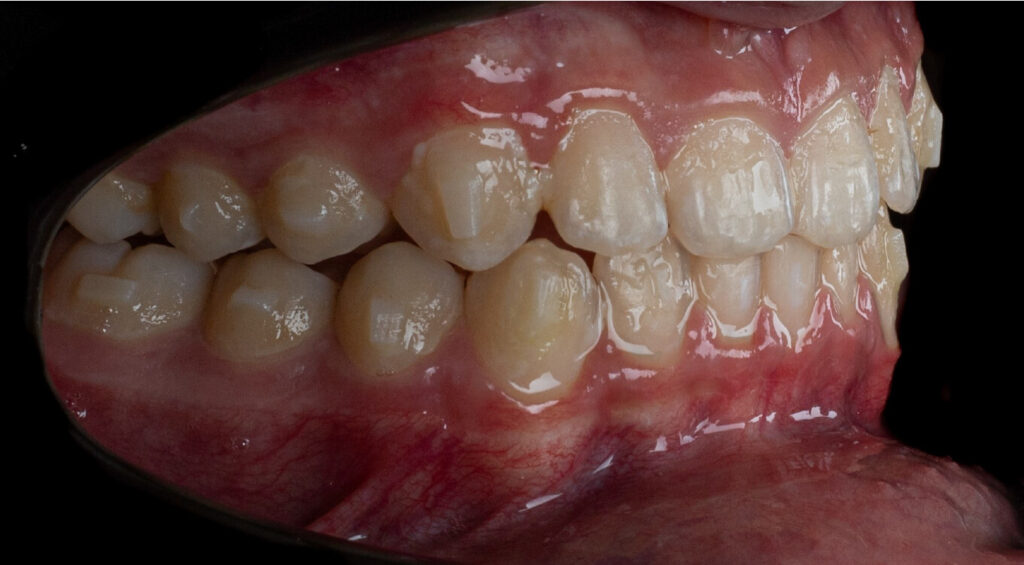

A 13-year-old male patient presented with a deep bite, characterized by near-complete coverage of the mandibular incisors. Clinical evaluation revealed bi-arch crowding, dental rotations, and proclination of the maxillary lateral incisors, contributing to the patient’s esthetic concerns. The facial profile was retrusive, consistent with mandibular retrognathism, and no significant periodontal abnormalities were detected.

The patient presented with a skeletal Class II relationship with bilateral molar and canine Class II and a Class II division 2 dental pattern. The deep bite was associated with anteroinferior crowding and an accentuated Curve of Spee. Facial analysis revealed good symmetry, a slightly increased lower facial third, and a convex profile characterized by mandibular and chin retrusion. Lip competence was mildly reduced, with a decreased nasolabial angle and mentalis hyperactivity, all of which compromised overall facial harmony.